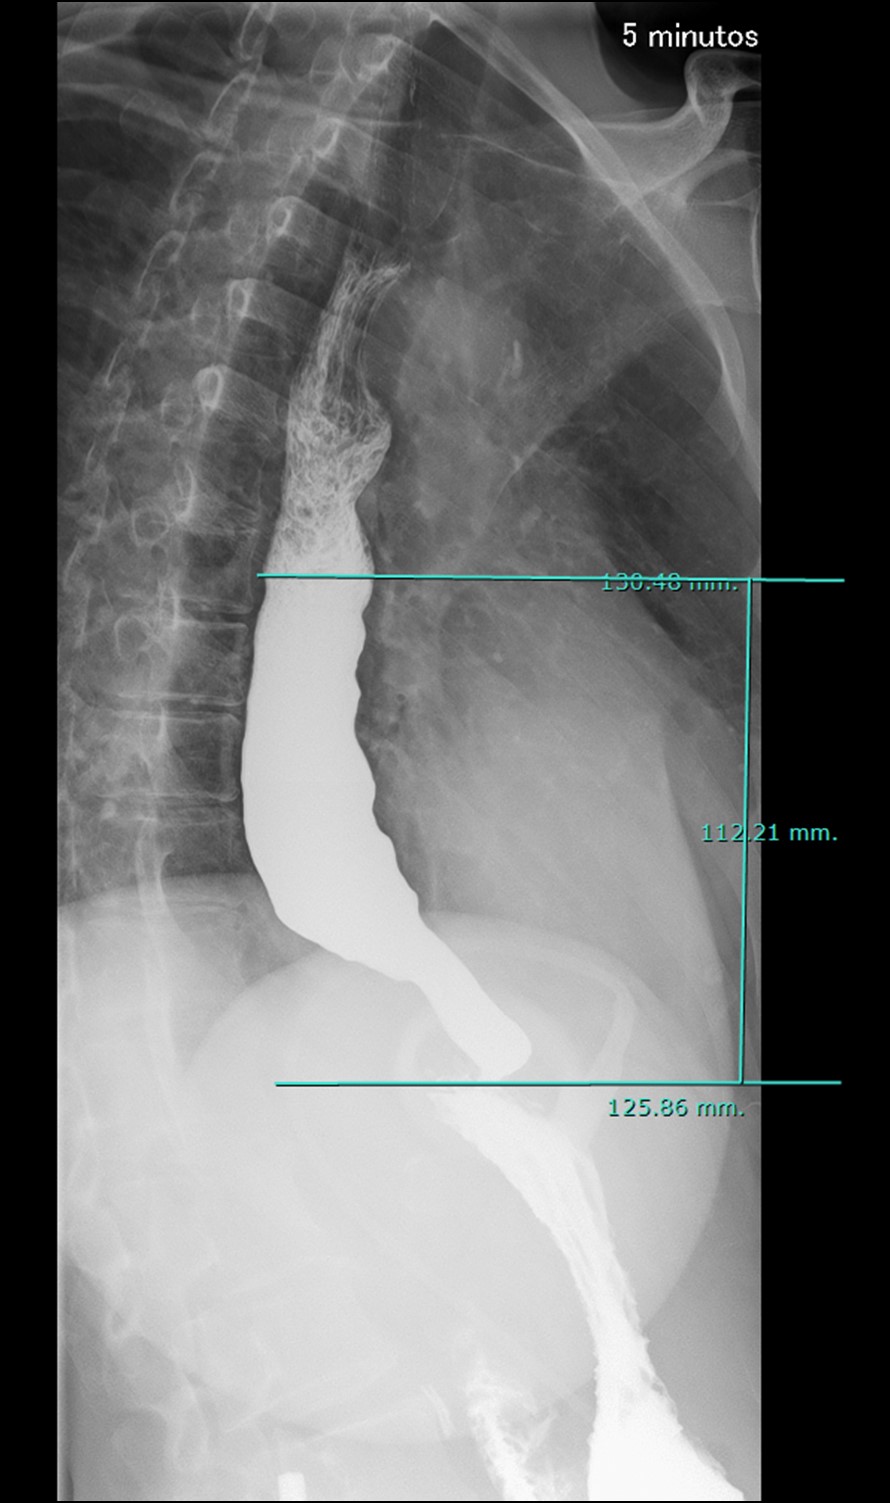

Esofagograma minutado

Presencia de banda gástrica en hipocondrio izquierdo. Esófago dilatado con un calibre máximo de 50 mm con tono y peristaltismo reducido. A los 5 minutos se observa una retención de columna de contraste en el esófago distal de hasta 112 mm (figuras 1 y 2).

Figura 2: Adquisición a los 5 minutos con columna de bario en esófago distal de hasta 112 mm.